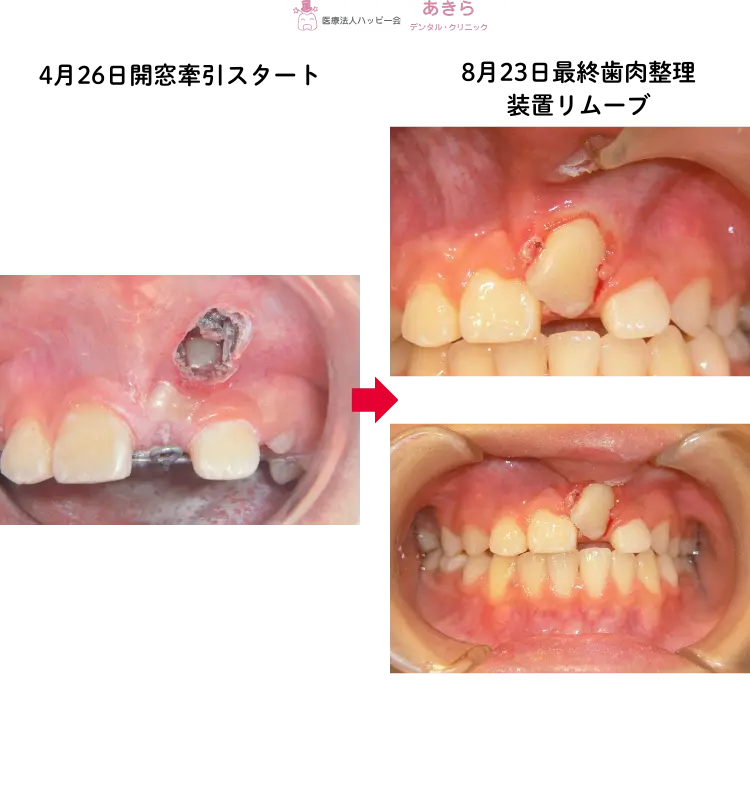

- 2019年4月 開窓牽引スタート。

- 2回装置を交換し、牽引を8月に終了